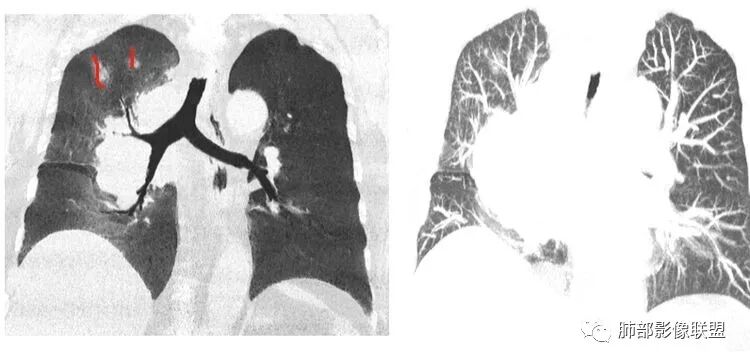

支气管狭窄,壁有侵犯

局限性中央间质增厚,考虑癌性淋巴管炎

部分区域有结节感

Coke with ice: 这个是标记的结节感吗?

南边: 奇怪,你们都不觉得这里有结节?

了: 气腔结节

毛勤香: 这个人有癌淋,有点结节感

Coke with ice: 嗯,不明显的结节感可以考虑用MPR和薄层结合起来看,会不会判断的更准一些